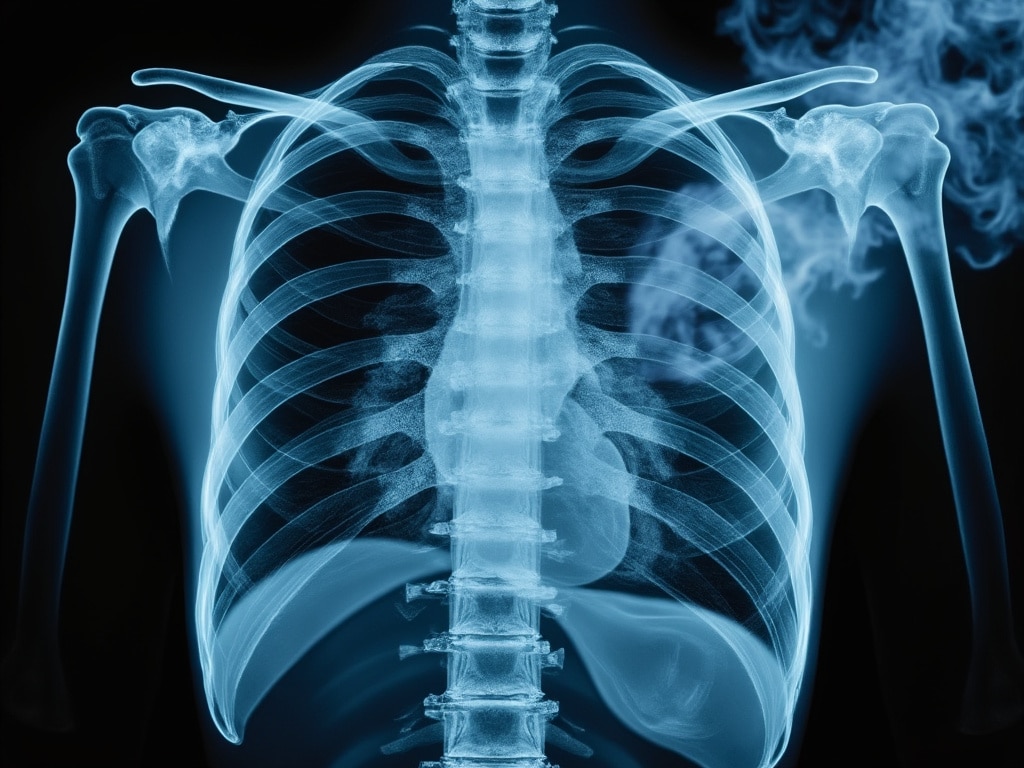

3. Risker för lungorna

Studier har visat att ångan från e-cigaretter kan orsaka irritation i lungorna och potentiellt leda till inflammation. Ett allvarligt, men ovanligt, tillstånd kopplat till vaping är EVALI (e-cigarette or vaping-associated lung injury), som kan orsaka allvarliga lungskador.

Är vape farligt för lungorna?

Vaping påverkar lungorna på flera sätt, även om det ofta marknadsförs som ett mindre skadligt alternativ till traditionella cigaretter. Även om e-cigaretter inte innehåller samma mängd skadliga ämnen som cigaretter, finns det risker med att inhalera de kemikalier som finns i e-vätskan. Ämnen som propylenglykol och vegetabilisk glycerin kan irritera luftvägarna, särskilt vid långvarig användning. Smakämnen som tillsätts i e-vätskor kan också bilda biprodukter vid upphettning som potentiellt skadar lungvävnaden.

Studier har visat att vissa användare av e-cigaretter har utvecklat lungrelaterade sjukdomar som bronkitliknande symtom, nedsatt lungfunktion och i extrema fall lungskador (kända som EVALI, e-cigarette or vaping product use-associated lung injury). Dessutom kan nikotin i vapeprodukter bidra till ökad inflammation i lungorna och förvärra befintliga luftvägssjukdomar.

Även om mer forskning behövs för att förstå långtidseffekterna av vaping på lungorna, är det tydligt att det inte är riskfritt. För den som vill skydda sin lungfunktion är det bäst att undvika både traditionella cigaretter och e-cigaretter.